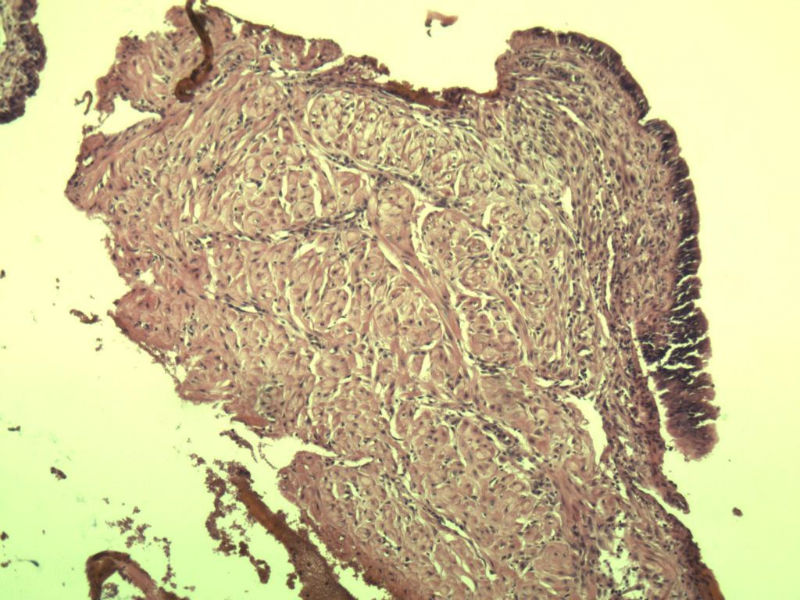

女 32岁 不规则阴道流血 一年  请各位老师看看 谢谢了

遵义医学院附属医院会诊结果    "复杂性增生伴非典型性 "

补充一下病史 病人10个月前因月经不规则行诊刮 诊断非典型性增生  上了曼月乐避孕环(好像是缓慢释放孕激素的那种),         都用激素治疗大半年了 还是这个样子 我还是觉得是癌  只有追踪一下以后病人的情况吧

高分化子宫内膜样癌

非典型复杂性子宫内膜增生,应了解雌孕激素情况。

子宫内膜复杂性非典型性增生,局灶区间质肉芽样(图5)及蜕膜样变,不够癌,建议临床查激素水平并追踪。

从照片看,没看到浸润的地方,我考虑是子宫内膜重度不典型增生。